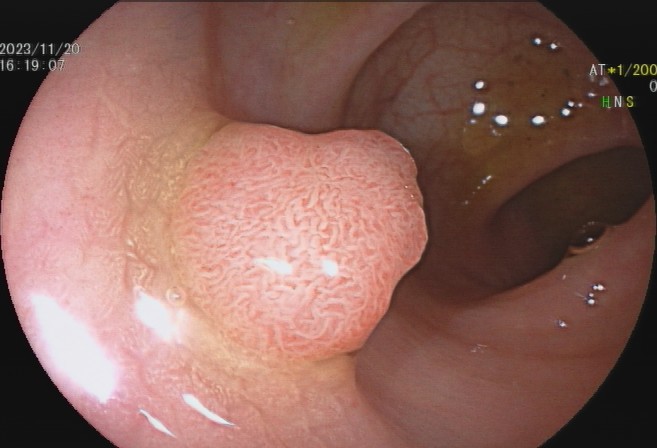

肠息肉是指突出于肠腔表面的隆起,在没有确定病理性质前统称为息肉,其发生率通常随年龄增加逐渐上升,病变部位以结直肠多发,与结直肠癌的发病有密切关系。

少数患者会发生便血,而结肠息肉很多的患者也可能会发生腹泻、黏液便、腹痛等症状,但这些症状无特异性,因此要确诊结肠息肉主要依赖结肠镜等检查,多数患者是在体检或因其他疾病做结肠镜时才被发现。

95%以上的结肠癌是从结肠息肉一步步转变而来,因此,结肠息肉一旦发现应该及时切除。发现息肉和早期肠癌,在内镜下就可以把这颗“定时炸弹”切除,创伤也小,对预期寿命几乎没有影响。